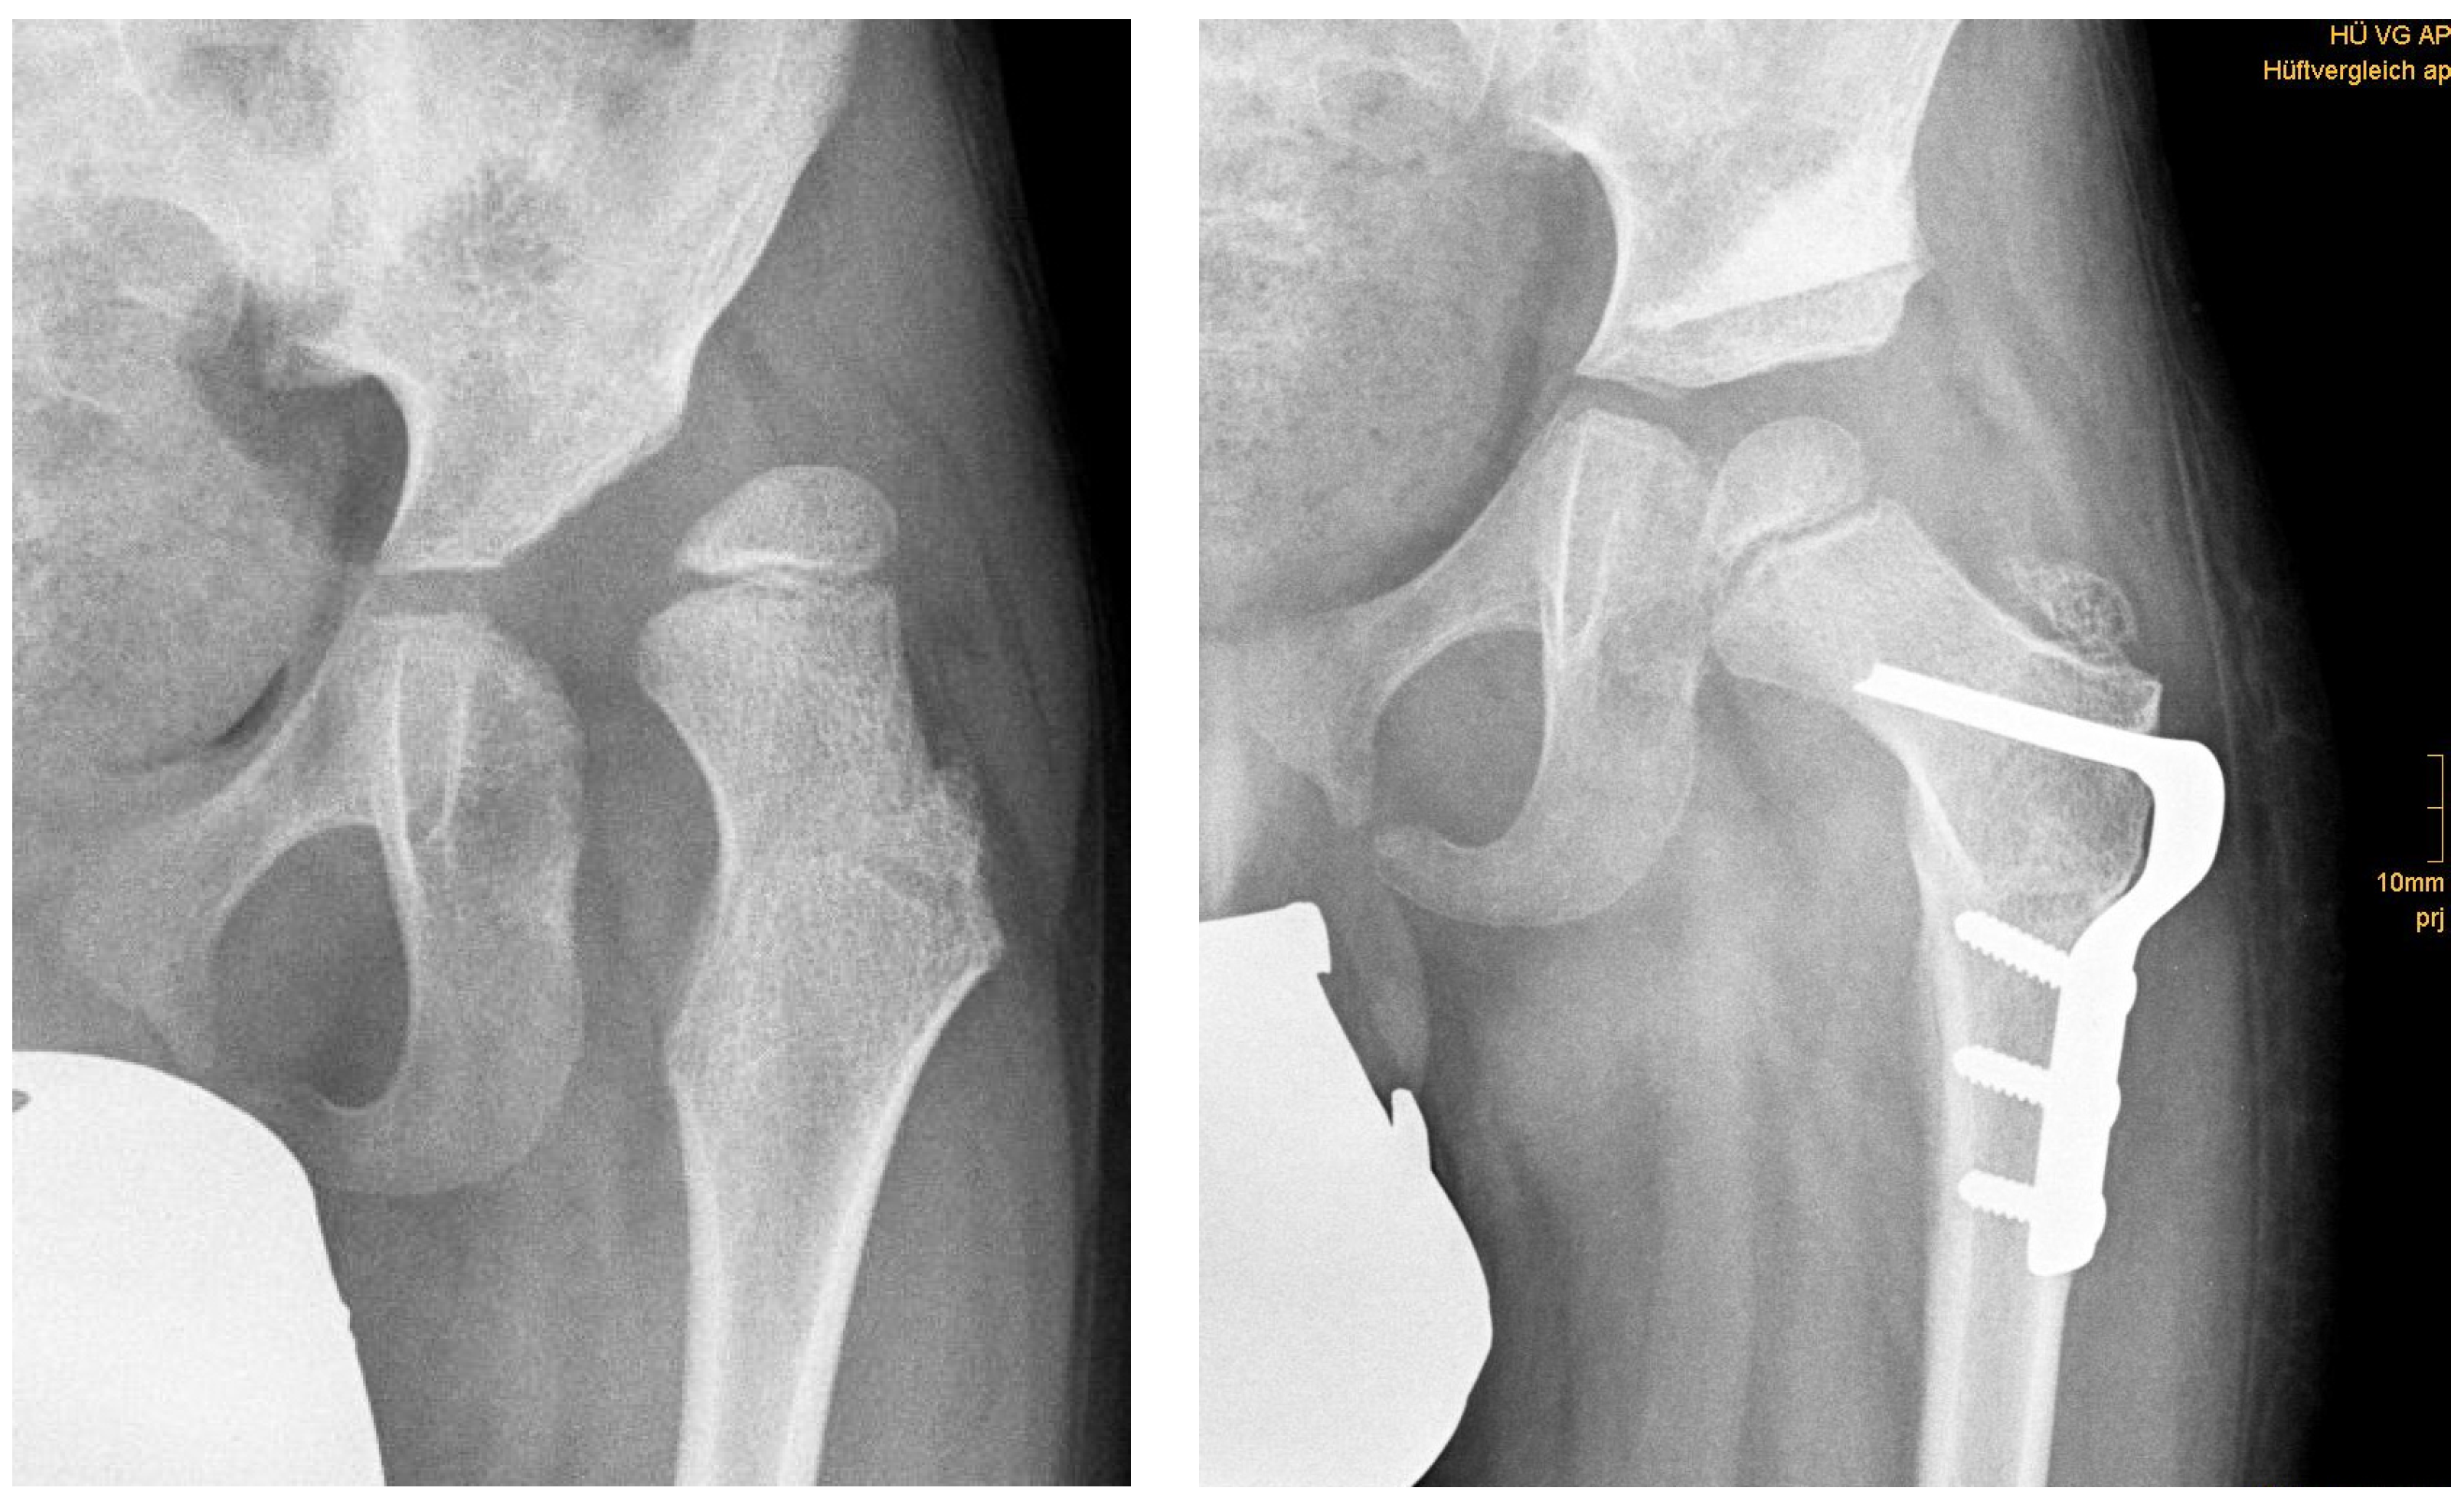

Three months after surgery, children with DDH showed significant decreased RMI compared with children with NDH in a two-sample Student’s t-test (2.77 ± 6.90% vs. 12.94 ± 13.50%; p = 0.011). More often an osteotomy of the iliac bone (Salter innominate, Pemberton, Chiari) was carried out in patients with DDH than with NDH (27 vs. 17; p < 0.001). In cases with combined one step iliac and femoral osteotomy, the residual RMI was significantly lower than in cases with osteotomy of the femur alone (7.02 ± 11.1% vs. 16.85 ± 4.71%; p < 0.001) (Table 4, Figure 1 and Figure 2).

Figure 1.

(left) Anteroposterior radiograph of a six-year-old male with NDH; (right) result 3 months postoperatively.